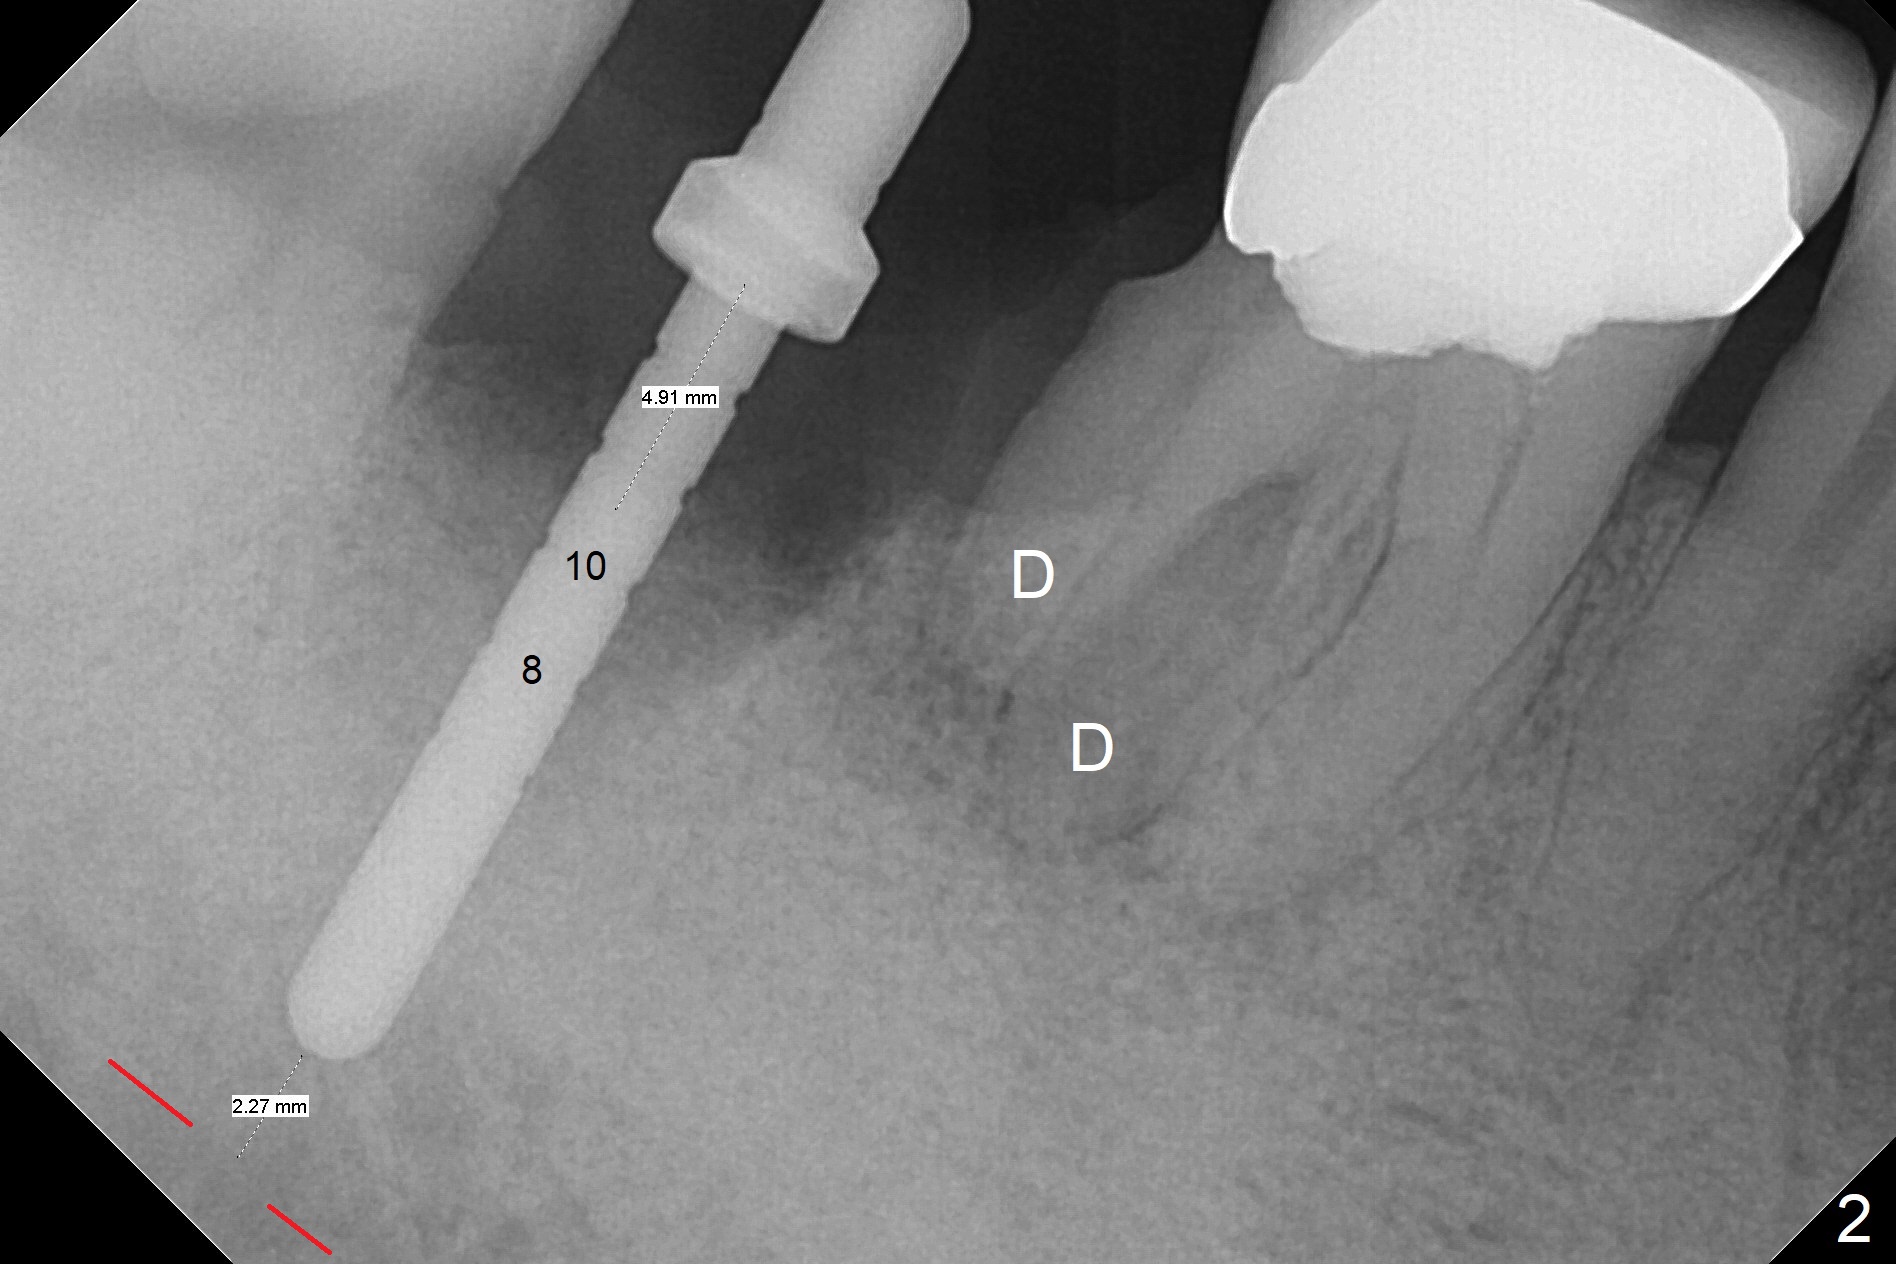

Although the tooth #30 has distobuccal root exposure (Fig.1 <), it is asymptomatic. In contrast the tooth #31 with the distoocclusal caries (*) is symptomatic. After use of 2 mm drill for 18 mm (lingual gingival margin), a calculated parallel pin is inserted (Fig.2 (D: 2 distal roots of the tooth #30)). It appears that a 11.5 mm long implant is appropriate for the site; a 5 mm cuff is expected. Following 4.8 mm drill, a 5.5x11.5 mm implant is placed initially (Fig.3) with an apical space (*) and clearance from the Inferior Alveolar Canal (red dashed line). The implant is placed deeper with placement of a 6.5x4(5) mm abutment and bone graft (*, Fig.4,5). After placement of collagen membrane over the graft, an immediate provisional is fabricated (Fig.6 P) with clearance from the opposing tooth (Fig.7 *). There is no bone loss 3.5 months postop (Fig.8). In fact the abutment has not been seated completely since its placement (Fig.4,5,8). The crown/abutment dislodges 3 years 3 months post cementation (Fig.9). The latter occurs for long incubation time because of opposing partial denture (Fig.10). After trimming proximal surfaces (Fig.11: arrowheads), the abutment remains incompletely seated (Fig.11) due to possible crestal bone interference (Fig.11 *). The smaller abutment by itself remains unseated (Fgi.12). One size small one is completely seated (Fig.13). Impression is taken. Two weeks later the abutment margin is supragingival. After screw torque at 20 Ncm, the crown is cemented with access hole. Excess cement is removed.